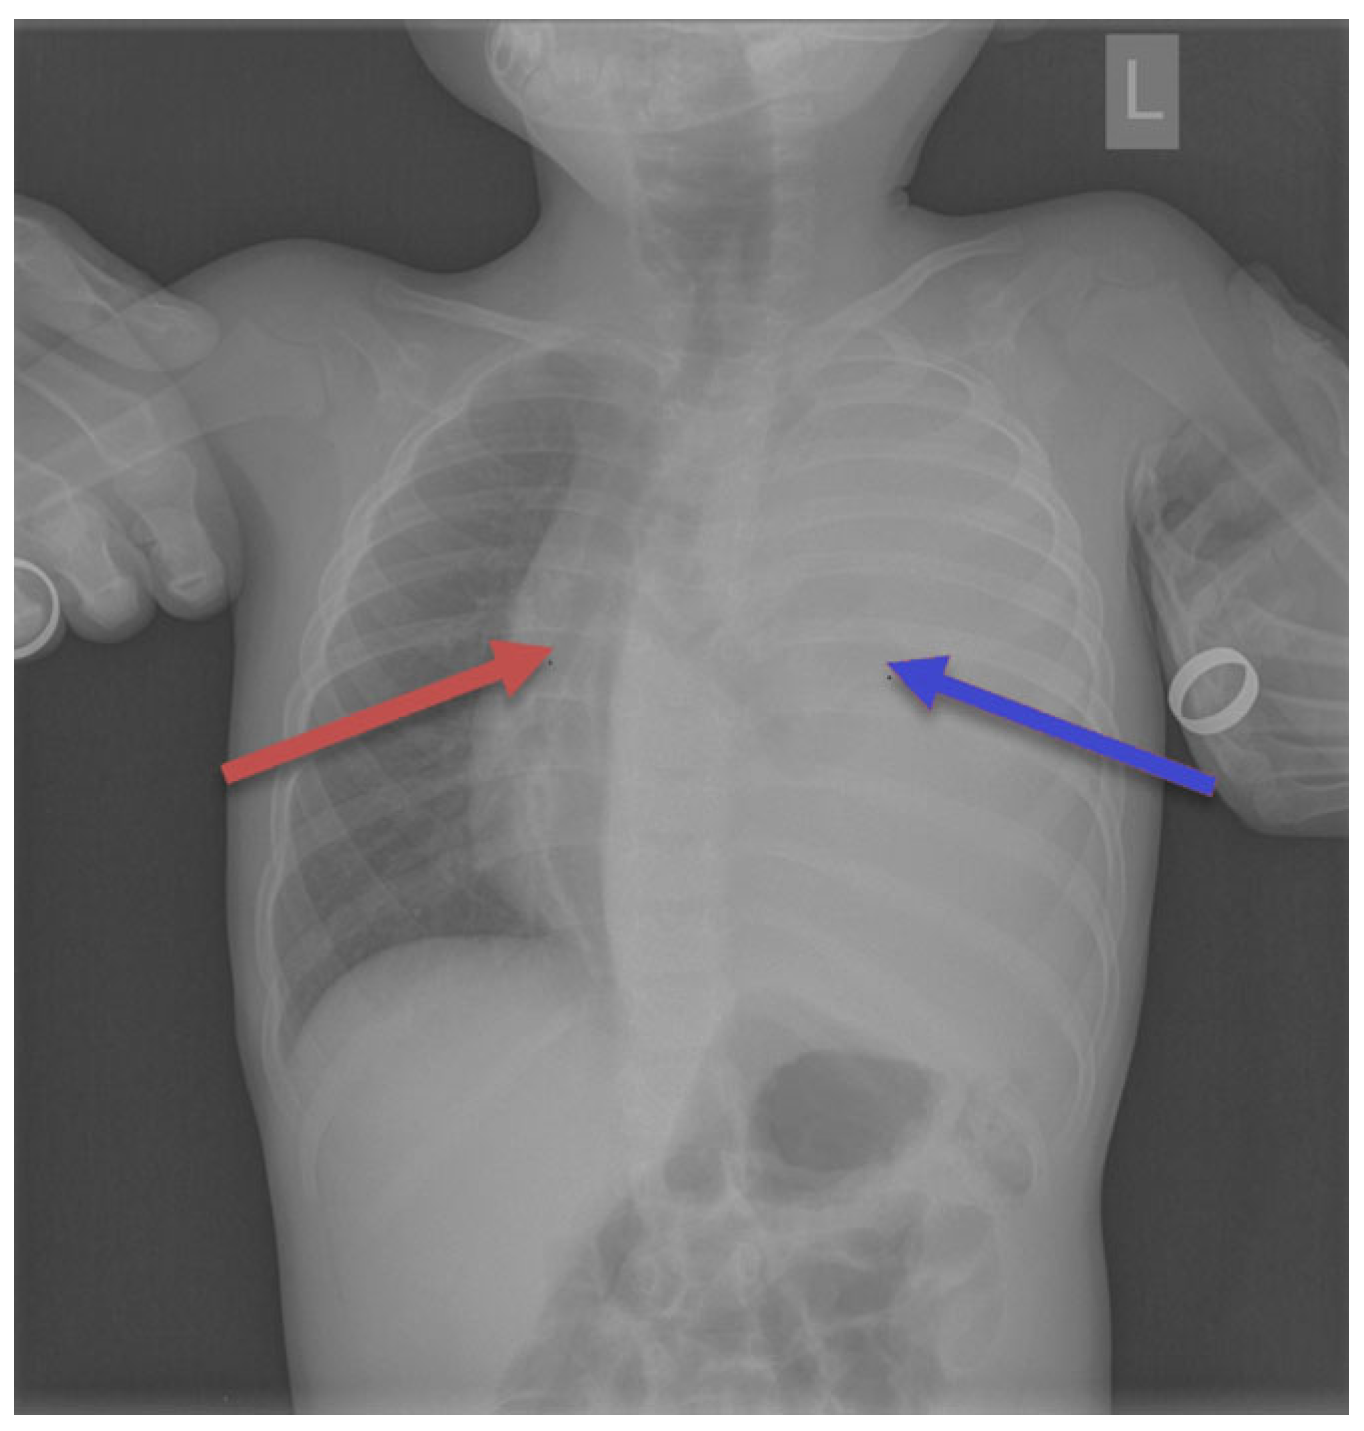

Seven children had a tumor located on the left side of the chest, and eight children on the right side. In seven children, the dimensions of the tumor were >10 cm; in five, they measured 5–10 cm; and in two patients, they were below 5 cm. In one patient, the dimensions were difficult to assess due to the occurrence of a massive pneumothorax. No bilateral lesions were found. Typical radiological findings are shown on Figure 2, Figure 3 and Figure 4.

Figure 4. Chest radiograph showed complete homogenous opacification of the left hemithorax (the blue arrow) with contralateral mediastinal and tracheal deviation (the red arrow).